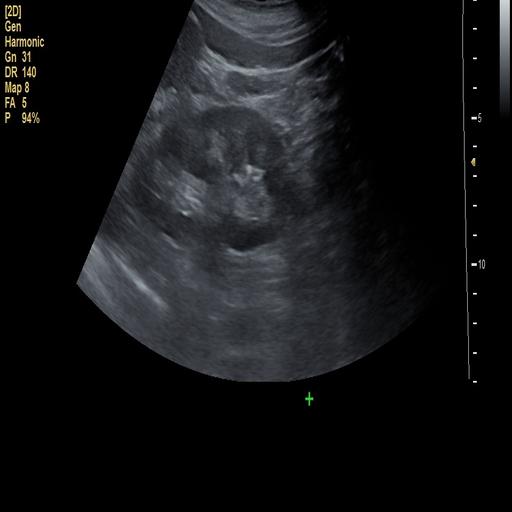

数据样例

正常肾脏样例